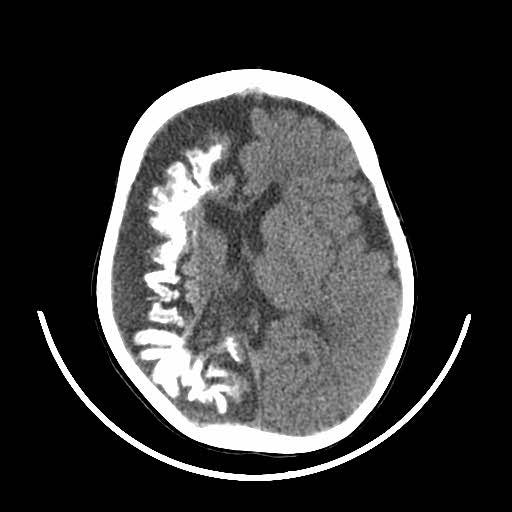

Patients suspected of SWS will have a CT or MRI scan. This will now typically be done if the patient is seen to have a Port-Wine Stain in the V1 distribution to assess for associated involvement in the brain.

The image above shows an example of what an MRI (top) and a CT scan (bottom) would look like in a patient with SWS. In the CT scan on the left side, you can see this white mark. This is caused by a process known as calcification where deposits of calcium phosphate build up in the brain, creating ‘brain stones’ that can increase in size, and potentially induce further neurological issues. In addition, you are also able to observe the size difference from the left to the right of the brain. This is known as brain atrophy. Both calcification and extent of brain atrophy are key factors in determining the severity of the neurological conditions in SWS. Emerging research by Great Ormond Street Hospital proposed targeting these abnormally high inter-cranial calcium deposits as a potential therapeutic pathways to reduce progression of cortical damage.